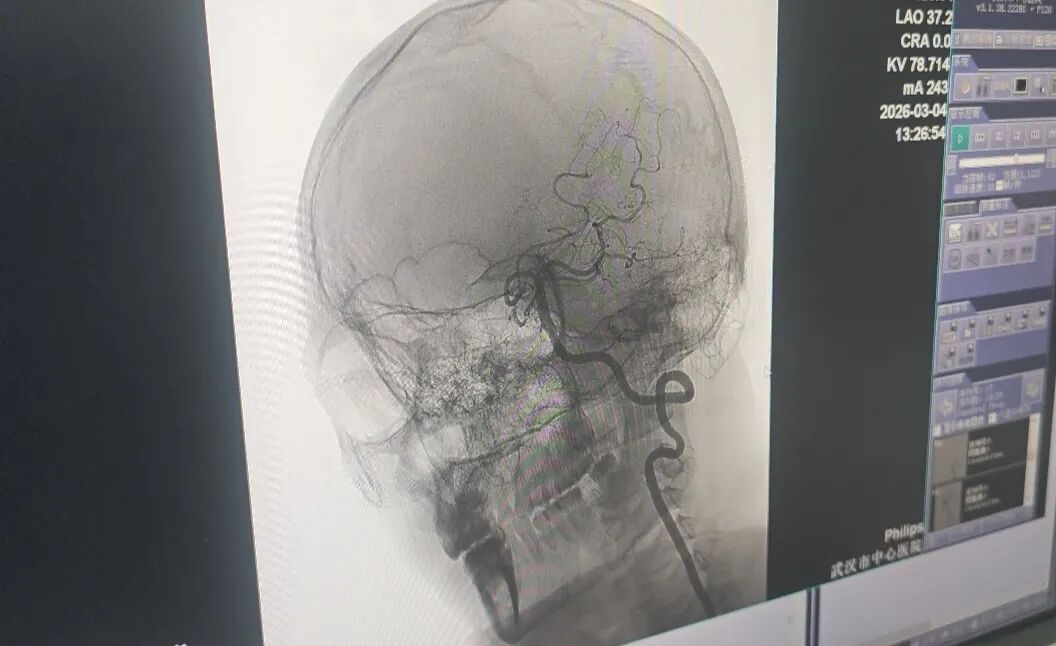

抢救团队考虑到患者椎动脉血管未完全闭塞,于是采用介入下动脉溶栓的方式,精准打通了堵塞的血管。

医生精准打通王先生堵塞的血管。记者李慧紫 摄